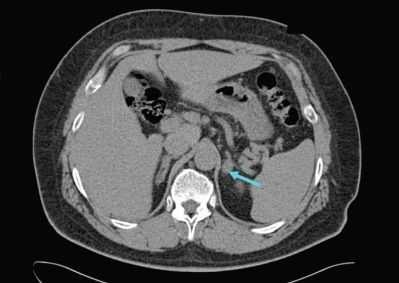

При совместном добавлении адреналина и ЛПНП количество метки, связанной с эндотелием, возрастало в 3 раза, а ее распределение свидетельствовало о более медленном проникновении в ткани по сравнению с ЛПНП без адреналина (см. рис. 1, табл. 2). Абсолютное большинство метки (см. табл. 2) располагалось в контакте с люминарной поверхностью эндотелиоцитов (прилипание и инвагинации). За 30 мин перфузии с адреналином в макрофаги проникало только 11% метки, при этом она концентрировалась исключительно в эндосомах (рис. 2, см. на вклейке), в то время как без адреналина метки в макрофагах фиксировалось в 4 раза больше (см. рис. 1), и почти половина ее располагалась уже в лизосомах. В этих опытах были выявлены некоторые особенности проникновения в миокард меченых ЛПНП, которые не поглощались целиком, а претерпевали частичное разрушение (лизис) на поверхности эндотелиоцитов. Это хорошо согласуется с данными о том, что липопро- теинлипаза способна связываться с мембранами эндотелиальных клеток через глюкозаминоглика- ны и одновременно взаимодействовать с ЛП [1]. В этом случае количество фермента определяет число ЛП частиц, которое он удерживает на поверхности клеток [13]. Таким образом, регулируется поступление главного энергетического материала — жирных кислот в миокард. Есть данные о том, что кар- диотоксическое действие катехоламинов обусловлено увеличением образования свободных радикалов [17]. Способность ЛП связывать свободные радикалы может лежать в основе их кардиопротек- торного эффекта [12, 16].

Добавление кортикостерона вызывало увеличение числа связанной с эндотелием метки почти в 5 раз по сравнению со всеми другими опытами с ЛПВП (см. рис. 1). Резкое усиление рецепторопос- редованного эндоцитоза (рис. 3, см. на вклейке) в эндотелии проявлялось в том, что метка накапливалась преимущественно в опушенных пузырьках (см. табл. 2). К концу эксперимента много метки располагалось около базальной поверхности эндотелия, где зафиксированы многочисленные картины открытия эндосом. Иногда скопления гранул располагались вблизи расширенных межклеточных контактов, что не исключало их выход, минуя эндотелиоциты. Принципиальное отличие опытов с кортикостероном и ЛПВП заключалось в том, что метка была обнаружена в интерстиции и макрофагах, хотя и в небольшом количестве (см. рис. 1). Неожиданной находкой явилось обнаружение ме-

а - ЛПНП; б - Ад + ЛПНП; в - Кс + ЛПНП; г - ЛПВП; д - Ад + ЛПВП; е - Кс + ЛПВП. ченых комплексов не только в эндотелии и интер- стиции, но и в просветах лимфатических сосудов, которые располагались в тесном сплетении с кровеносными капиллярами (в подсчетах эту метку не учитывали).